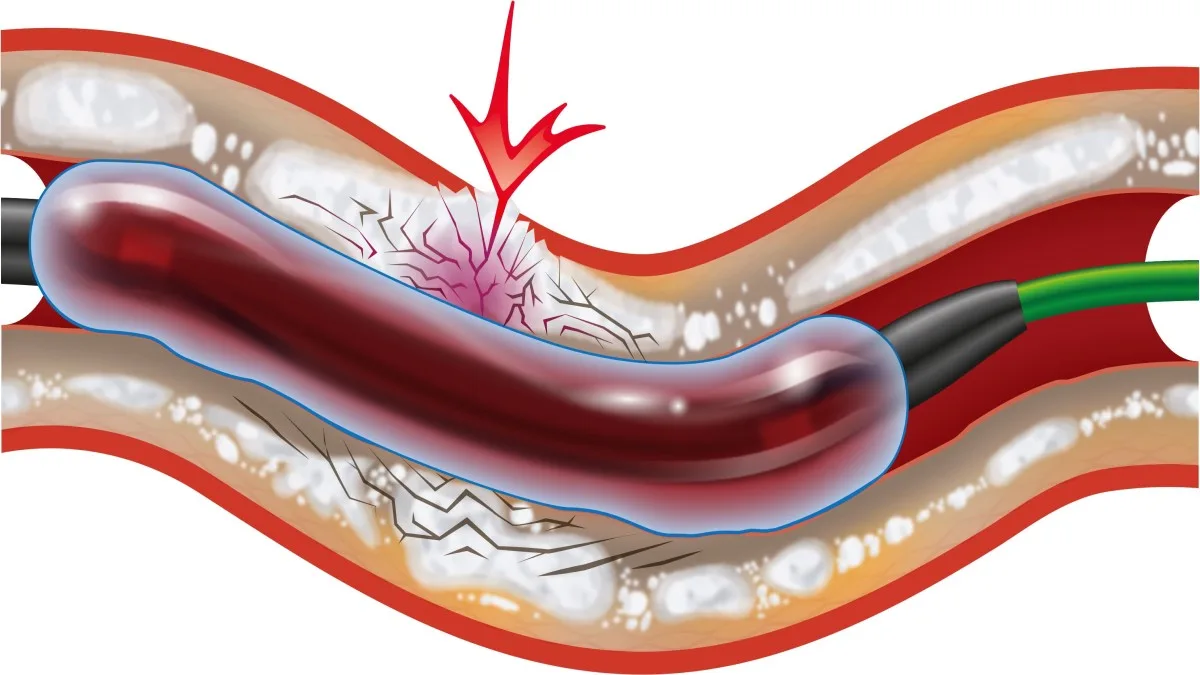

- IVL ( لیتوتریپسی داخل عروقی)

- نکات مهم:

- نتیجه گیری: